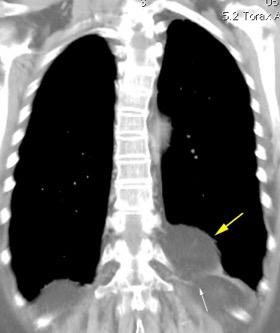

25. ELEVACIÓN UNILATERAL. TEP

Tromboembolismo pulmonar Diafragma elevado 20%